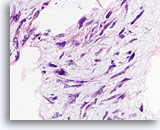

Typische ductale cellen, Borst FNA, Celblok.

Deze naaldspoeling van de patiënt in afbeelding 5 toont benigne ductale cellen als eenlagige epitheelstroken aan de rechterkant van de afbeelding. Aan de linkerkant ziet u een gebied met typische hyperplasie. De stratificatie van de cellen in dit gebied kan niet worden verklaard door tangentieel snijden. Met deze kleine vergroting kunt u de spleetachtige ruimten tussen de stratificerende ductale cellen zien, Ook kenmerkend voor typische ductale hyperplasie is de aanwezigheid van een mengsel van cellen met verschillende cytologische kenmerken (myoepitheliale cellen) in de stratificerende populatie.

Typische ductale cellen, Borst FNA, Celblok.

Deze naaldspoeling van de patiënt in afbeelding 5 toont benigne ductale cellen als eenlagige epitheelstroken aan de rechterkant van de afbeelding. Aan de linkerkant ziet u een gebied met typische hyperplasie. De stratificatie van de cellen in dit gebied kan niet worden verklaard door tangentieel snijden. Met deze kleine vergroting kunt u de spleetachtige ruimten tussen de stratificerende ductale cellen zien, Ook kenmerkend voor typische ductale hyperplasie is de aanwezigheid van een mengsel van cellen met verschillende cytologische kenmerken (myoepitheliale cellen) in de stratificerende populatie.

Typische ductale cellen, Borst FNA, Celblok.

Let op het mengsel van donkerder en lichterkleurende kernen en op de langwerpige ruimten. Bij typische ductale hyperplasie hebben de cellen de neiging om zich langs de as van de ruimten te groeperen (pijlen). Een andere nuttig diagnostisch kenmerk is de uitlijning van de lange as van de kernen van aangrenzende cellen, met een stromings- of vaag patroon van een ‘school vissen’ (open pijl). Deze kenmerken die duidelijk zichtbaar zijn bij een relatie kleine vergroting in histologische coupes, kunnen moeilijk of helemaal niet zichtbaar zijn in cytologische preparaten.

Typische ductale cellen, Borst FNA, Celblok.

Let op het mengsel van donkerder en lichterkleurende kernen en op de langwerpige ruimten. Bij typische ductale hyperplasie hebben de cellen de neiging om zich langs de as van de ruimten te groeperen (pijlen). Een andere nuttig diagnostisch kenmerk is de uitlijning van de lange as van de kernen van aangrenzende cellen, met een stromings- of vaag patroon van een ‘school vissen’ (open pijl). Deze kenmerken die duidelijk zichtbaar zijn bij een relatie kleine vergroting in histologische coupes, kunnen moeilijk of helemaal niet zichtbaar zijn in cytologische preparaten.